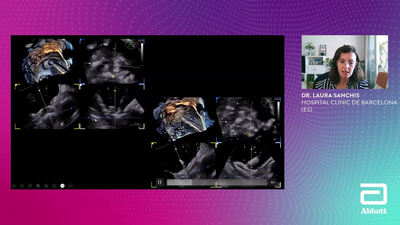

Case Parade | Mitral Focus